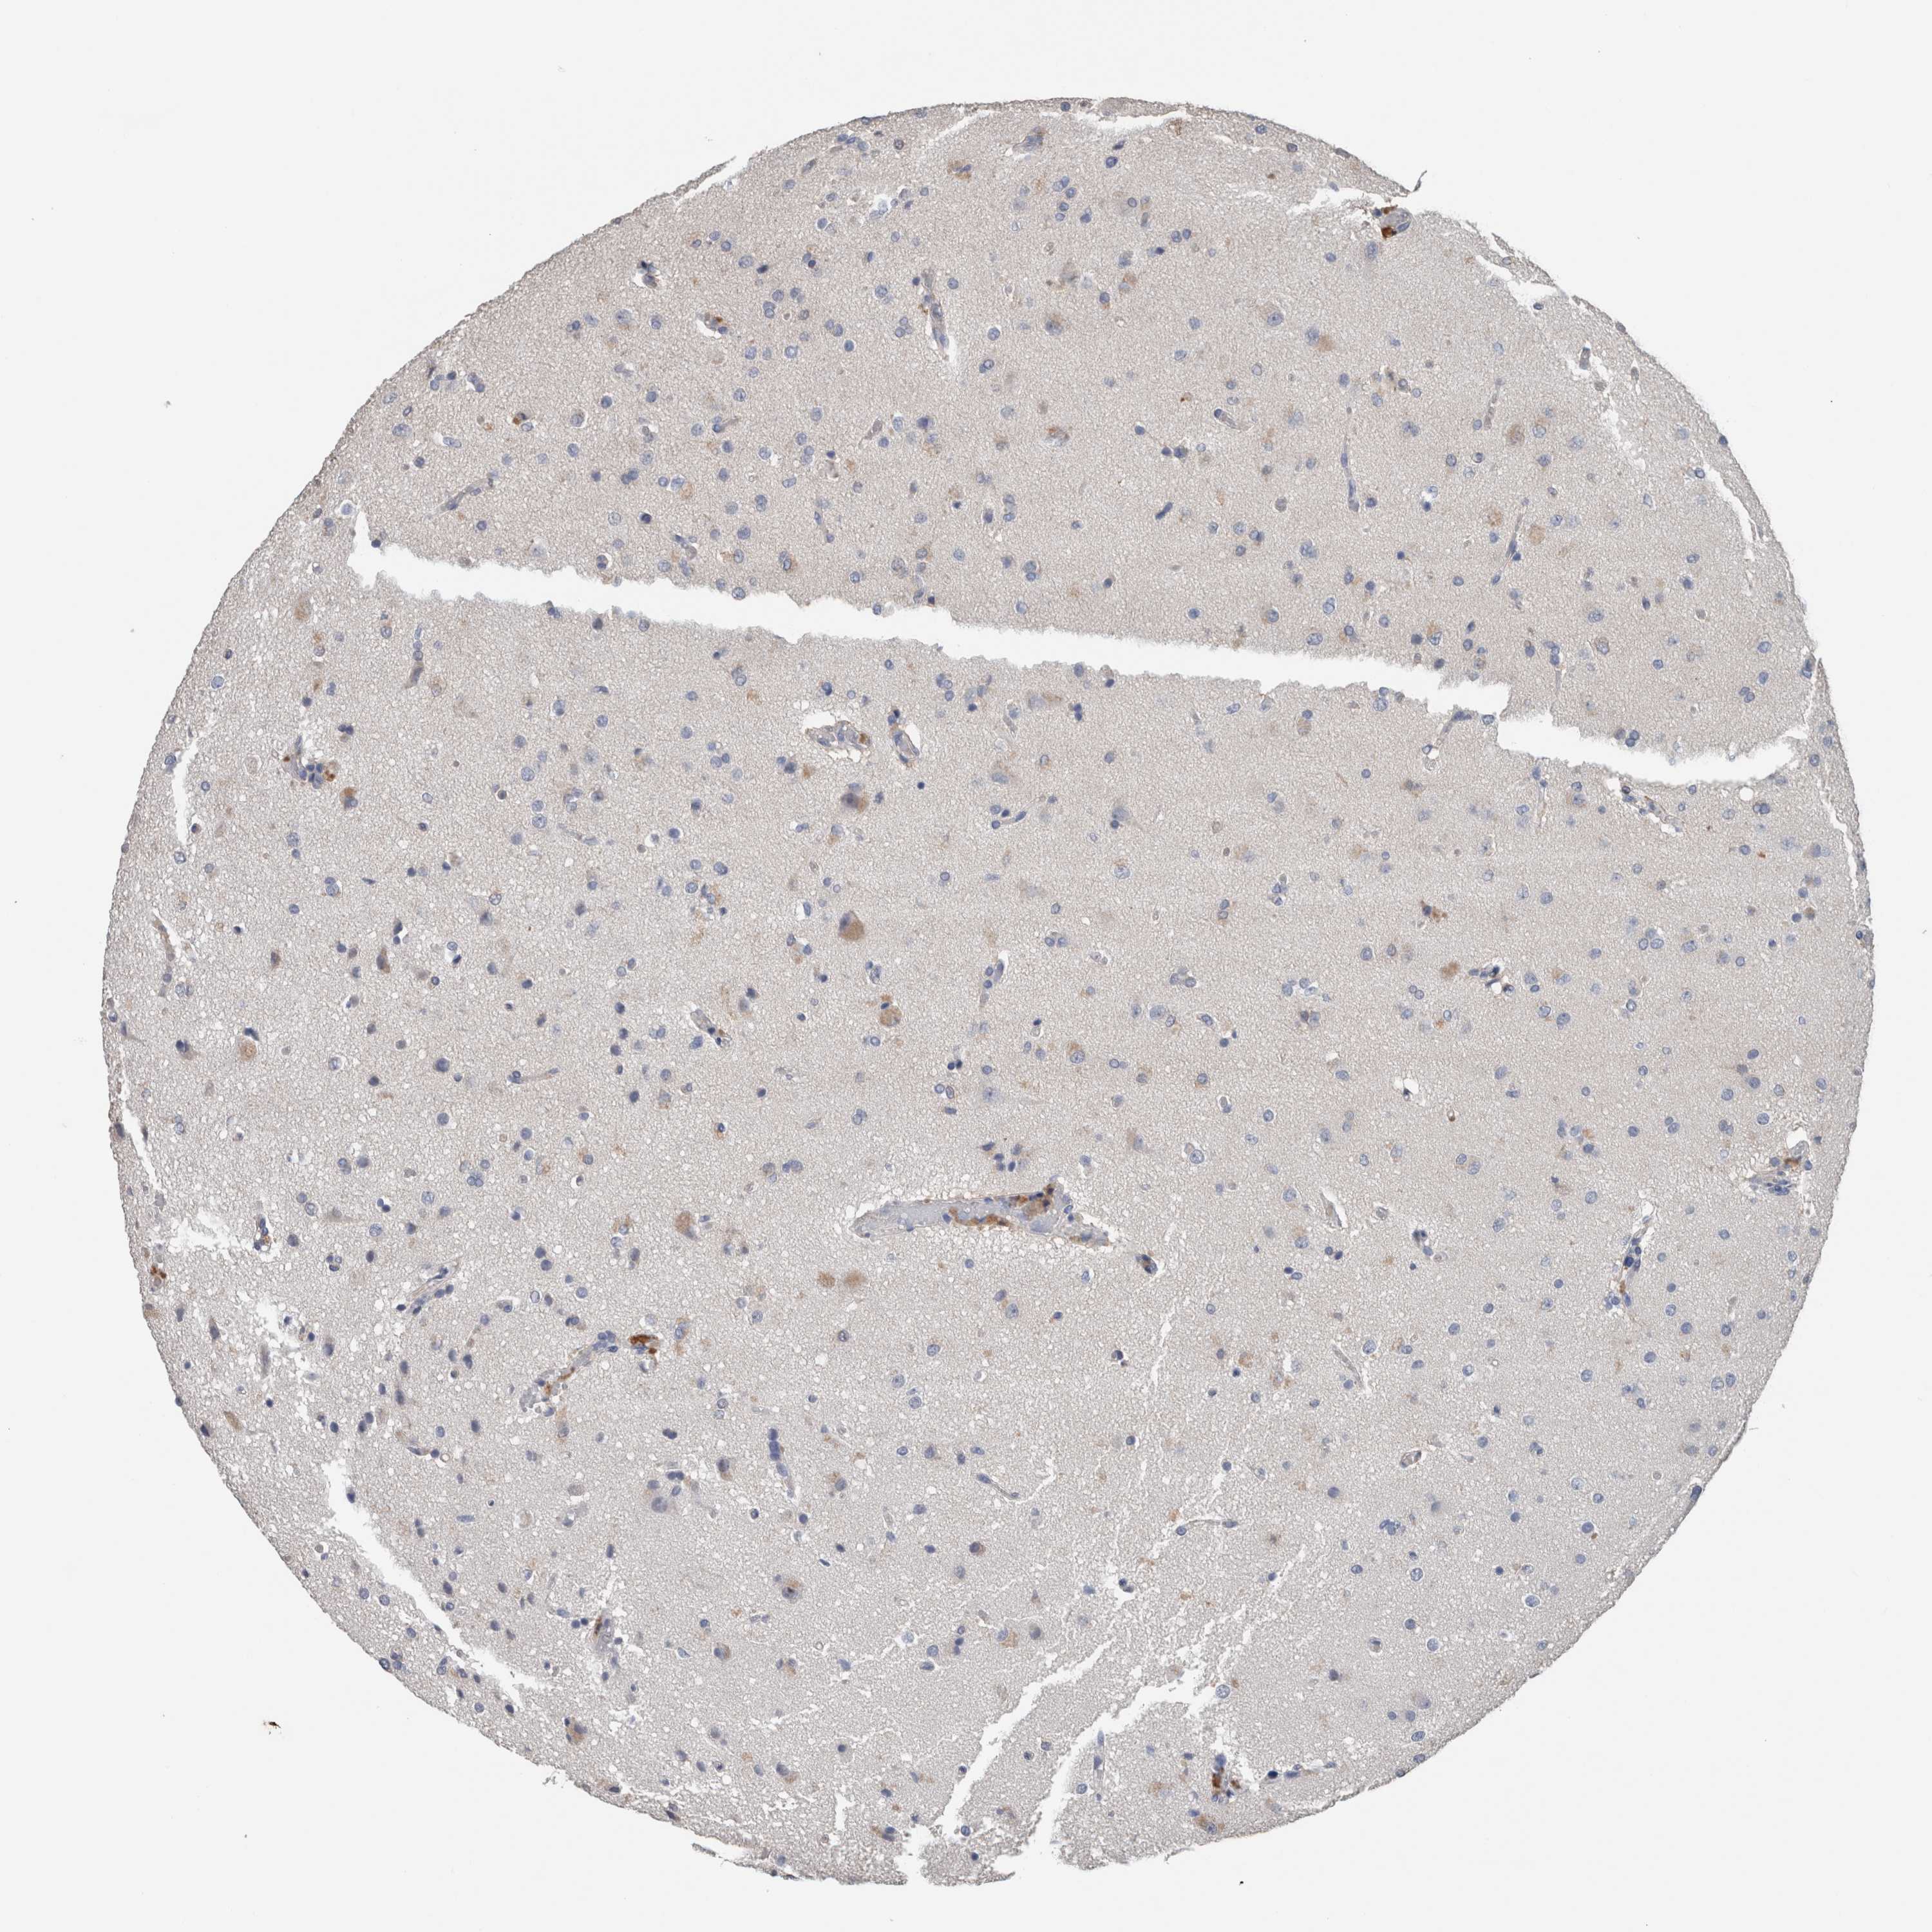

GLIOMA - Protein expressioni

A mouse-over function shows sample information and annotation data. Click on an image to view it in a full screen mode. Samples can be filtered based on level of antibody staining by selecting one or several of the following categories: high, medium, low and not detected. The assay and annotation is described here.

Antibody stainingi

Antibody staining in the annotated cell types in the current human tissue is reported as not detected, low, medium, or high, based on conventional immunohistochemistry profiling in selected tissues. This score is based on the combination of the staining intensity and fraction of stained cells.

Each image is clickable and will lead to virtual microscopy that enables deeper exploration of all samples and also displays staining intensity scores, fraction scores and subcellular localization as well as patient and tissue information for each sample.

Antibody HPA024343

Antibody CAB026182

Staining

High

Medium

Low

Not detected

Intensity

Strong

Moderate

Weak

Negative

Quantity

>75%

75%-25%

<25%

None

Location

Nuclear

Cytoplasmic/membranous

Cytoplasmic/membranous,nuclear

Glioma, malignant, High grade

Glioma, malignant, Low grade